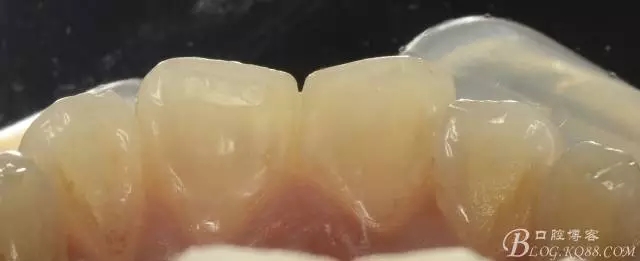

1)術前照

舌側觀

去腐后唇側照,僅剩透明的釉質?。?!

去腐后舌側照片:

沒有牙本質支撐的釉質是多么的晶瑩剔透,透得你舍不得傷害它!

術后即刻照,發(fā)現(xiàn)兩中切牙近中切角區(qū)明顯發(fā)白??

前牙區(qū),去腐后僅剩薄層釉質的情況,從美觀以及保存牙科學上來講,建議保留該透明的釉質層。